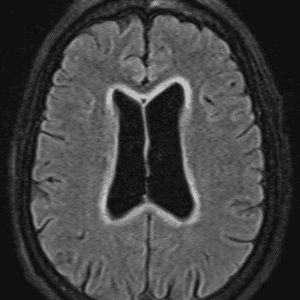

Case #27

Neuromyelitis optica (NMO)